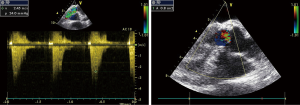

Surface echocardiography was performed. The aortic valve leaflets of the experimental animals freely opened and closed, their surface was smooth, and no abnormal echo was observed. The position, echo signal, and movement of the valve leaflets were not abnormal. Flow and Doppler showed that the blood flow velocity through the artificial heart valve flap was normal, but a little lower in the experimental group. No significant reflux was observed in each valve (Figure 4). The echocardiographic results and hemodynamics were comparable between the 2 groups, except that the experimental group showed slightly lower left ventricular systolic pressure (42.0±14.6 vs. 45.2±13.1 mmHg, P<0.05) and lower pulmonary artery pressure (8.3±0.6 vs. 11.5±4.4 mmHg) (Tables 6,7).